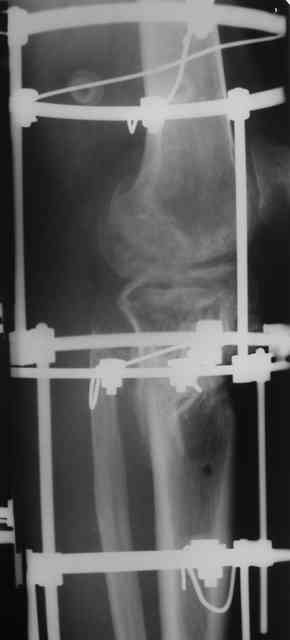

Р-граммы и фото за 4.05.2007 - 7-е сутки после операции.

Ход операции - линейным разрезом по передней поверхности голени обнажена зона ложного сустава большеберцовой кости. От кости отсепарованы медиально м/ткани. Из зоны ложного сустава убраны рубцовые ткани, мобилизован дистальный отломок. По передней поверхности удалены два осколка, связанных грануляциями. Произведено удаление грануляционной ткани из проксимального отломка (на вид сине-серого цвета), "чистого" гноя не было. Затем произведено наложение аппарата и репозиция отломков. По передне-медиальной поверхности образовался дефект до 4х2х2 см + полость в проксимальном отломке. Удаленные осколки очищены от грануляций, уложены в место дефекта, зажаты между отломками. После иссечения раны по передней поверхности, находящейся рядом с операционной раной, последняя ушита с большим натяжением.

Перелом мыщелка сросся. Проксимальный отломок очень порозный.

На перевязках - из раны небольшое кол-во сукровичного отделяемого. Отек голени умеренный, состояние кожи на фото.

Аппарат видел, репозиции не заметил. О "наложенном" аппарате: спицы в проксимальном отломке б\берцовой кости проведены очень низко, и опять только две, как и в первом аппарате. Почему только одна спица в дистальном парафрактурном кольце? Проксимальная база на бедре должна улучшить стабильность проксимального фрагмента tibia? Ничего подобного двумя спицами в одной базе при таком длинном рычаге вы не добьетесь, а вот совсем потерять движения в коленном суставе они почти гарантируют.

О репозиции: мыщелок сросся и слава Богу, но основные отломки фиксированы в вальгусном положении, собственно как и было, это критично. В чем состояла репозиция?

Провести еще одну спицу в проксимальном кольце дистального модуля. Между ними (модулями) убрать штанги ... "через колено" устранить варус и зафиксировать тремя резьбовыми штангами.